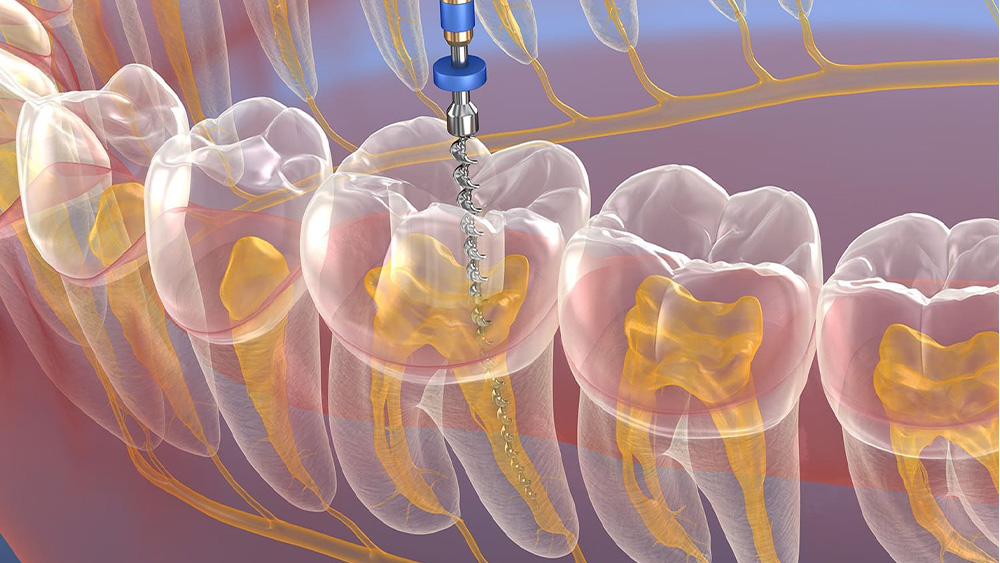

根管治療は、歯の内部にある神経や血管が通る「根管」という細い管が細菌に感染して炎症を起こしたり、壊死してしまったりした場合に行う治療です。

感染した神経や汚染物質を丁寧に取り除き、根管内をきれいに消毒し、薬剤で密閉することで、抜歯を避けてご自身の歯を残すことを目指します。

また、根管の清掃には、柔軟性に優れ、複雑な根管の形にもフィットしやすいニッケルチタンファイルを使用しています。

これにより、根管の壁を傷つけにくく、効率的かつ安全に感染物質を取り除くことを目指しています。

歯の内部にある神経や血管が細菌に感染し、炎症や壊死を起こしている場合に行う一般的な根管治療です。

感染した組織を丁寧に除去し、根管内を徹底的に清掃・消毒します。

その後、根管内を薬剤で緊密に充填し、細菌が再び侵入するのを防ぎます。

これにより、歯の痛みを取り除き、抜歯を避けながらご自身の歯を保存することを目指します。